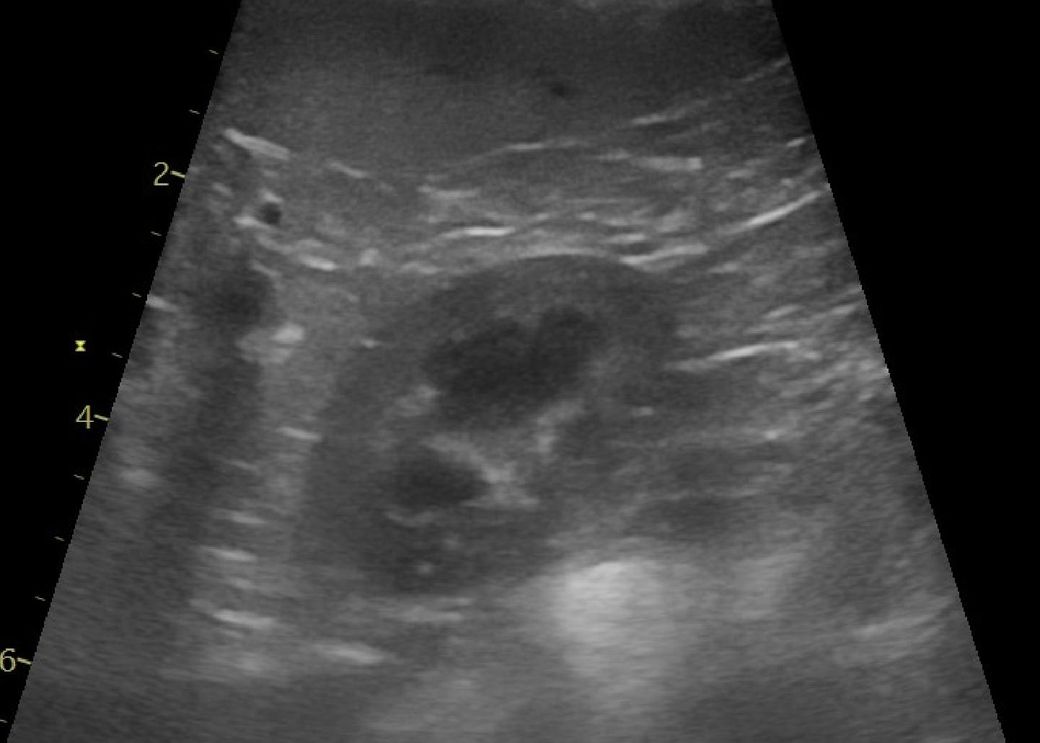

강아지 신장결석 칼슘옥살 스트루바이트 둘중 어느것 같아보이는지요?

강아지 신장결석 칼슘옥살 스트루바이트 둘중 어느것 같아보이는지요? 그냥 보시기에 만약에 판별이 가능하다면 알려주심 정말 감사하겠습니다. 병원만 3곳 다녔고 소변검사에 방광천자 제외하고 전부다 해봤는데 현재 6개월이 넘어갔는데 무슨 결석인지도 모르는 상태고 결석 크기는 신장 양쪽에 점점 커지고 있는 상황이라 이대로는 가만 있을수가 없어서 이렇게나마 질문글 올립니다.. 부디 알려주심 정말 한생명 살리는샘치고 정말 감사하겟습니다.

안녕하세요. 박창민 수의사입니다. 초음파 검사로 결석이 있는지, 위치나 크기, 개수, 형태 같은 정보는 확인할 수 있지만 결석의 정확한 종류나 성분까지는 알 수 없으며, 결석의 성분을 확인하려면 결석을 직접 채취해 분석하거나 소변 검사, X-ray, CT 등의 추가 검사가 필요합니다. 감사합니다.